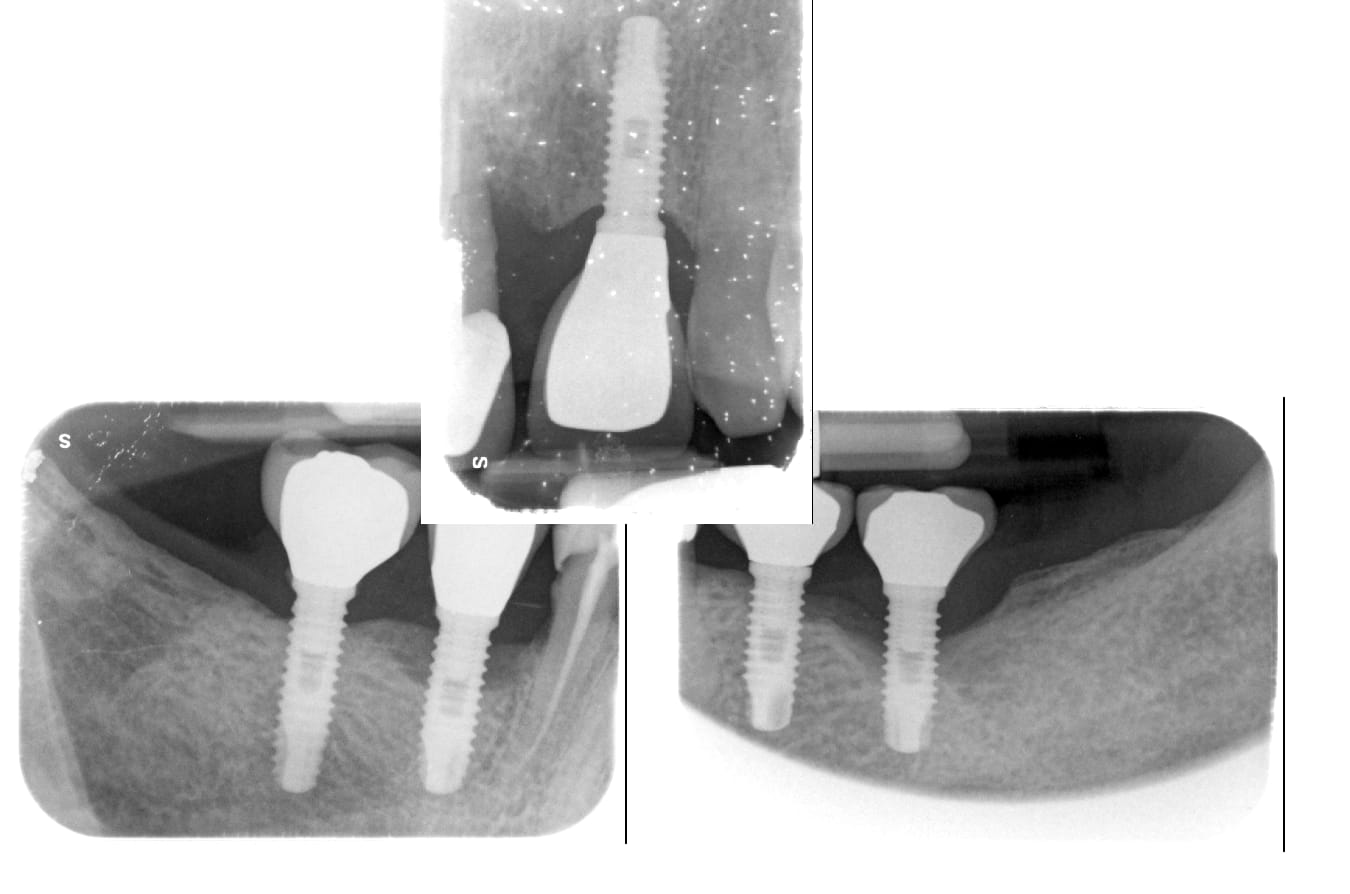

Sauriez-vous de quels implants il peut s'agir ?

J'ai enfin revu le patient, voici les rétro-alvéolaires !

J'ai contacté le service de maxillo où ça a été posé, et on me dit du MIS 3.5 à hexagone externe...

moi je dirais plutôt du néodent hex externe titamax HE

Est-ce que tu penses que ce pourrait être ça : https://osseosource.com/biocom-external-hexagon-standard-platform-4-1-/p-106.html

Oui c’est aussi possible….très peu de différence entre ces implants…